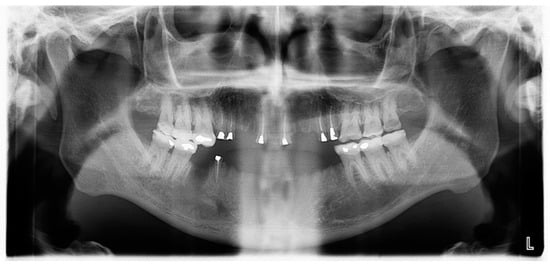

2.1. Clinical and Radiological Examination

- Pre-prosthetic care: exodontia, endodontic and restorative treatments were performed under general anesthesia. The following procedures were performed: endodontic treatment and bonded amalgam restorations for overdenture abutments of teeth numbers 11, 14, 15, 21, 24, 25 and 45 and exodontia of 46, 44, 43, 41, 33, 34, 35, 23, 22, 13 and 12 (Figure 6). The TRPD were placed on the day of surgery and a postoperative consultation was performed the following day to evaluate and adjust the prostheses (Figure 7).